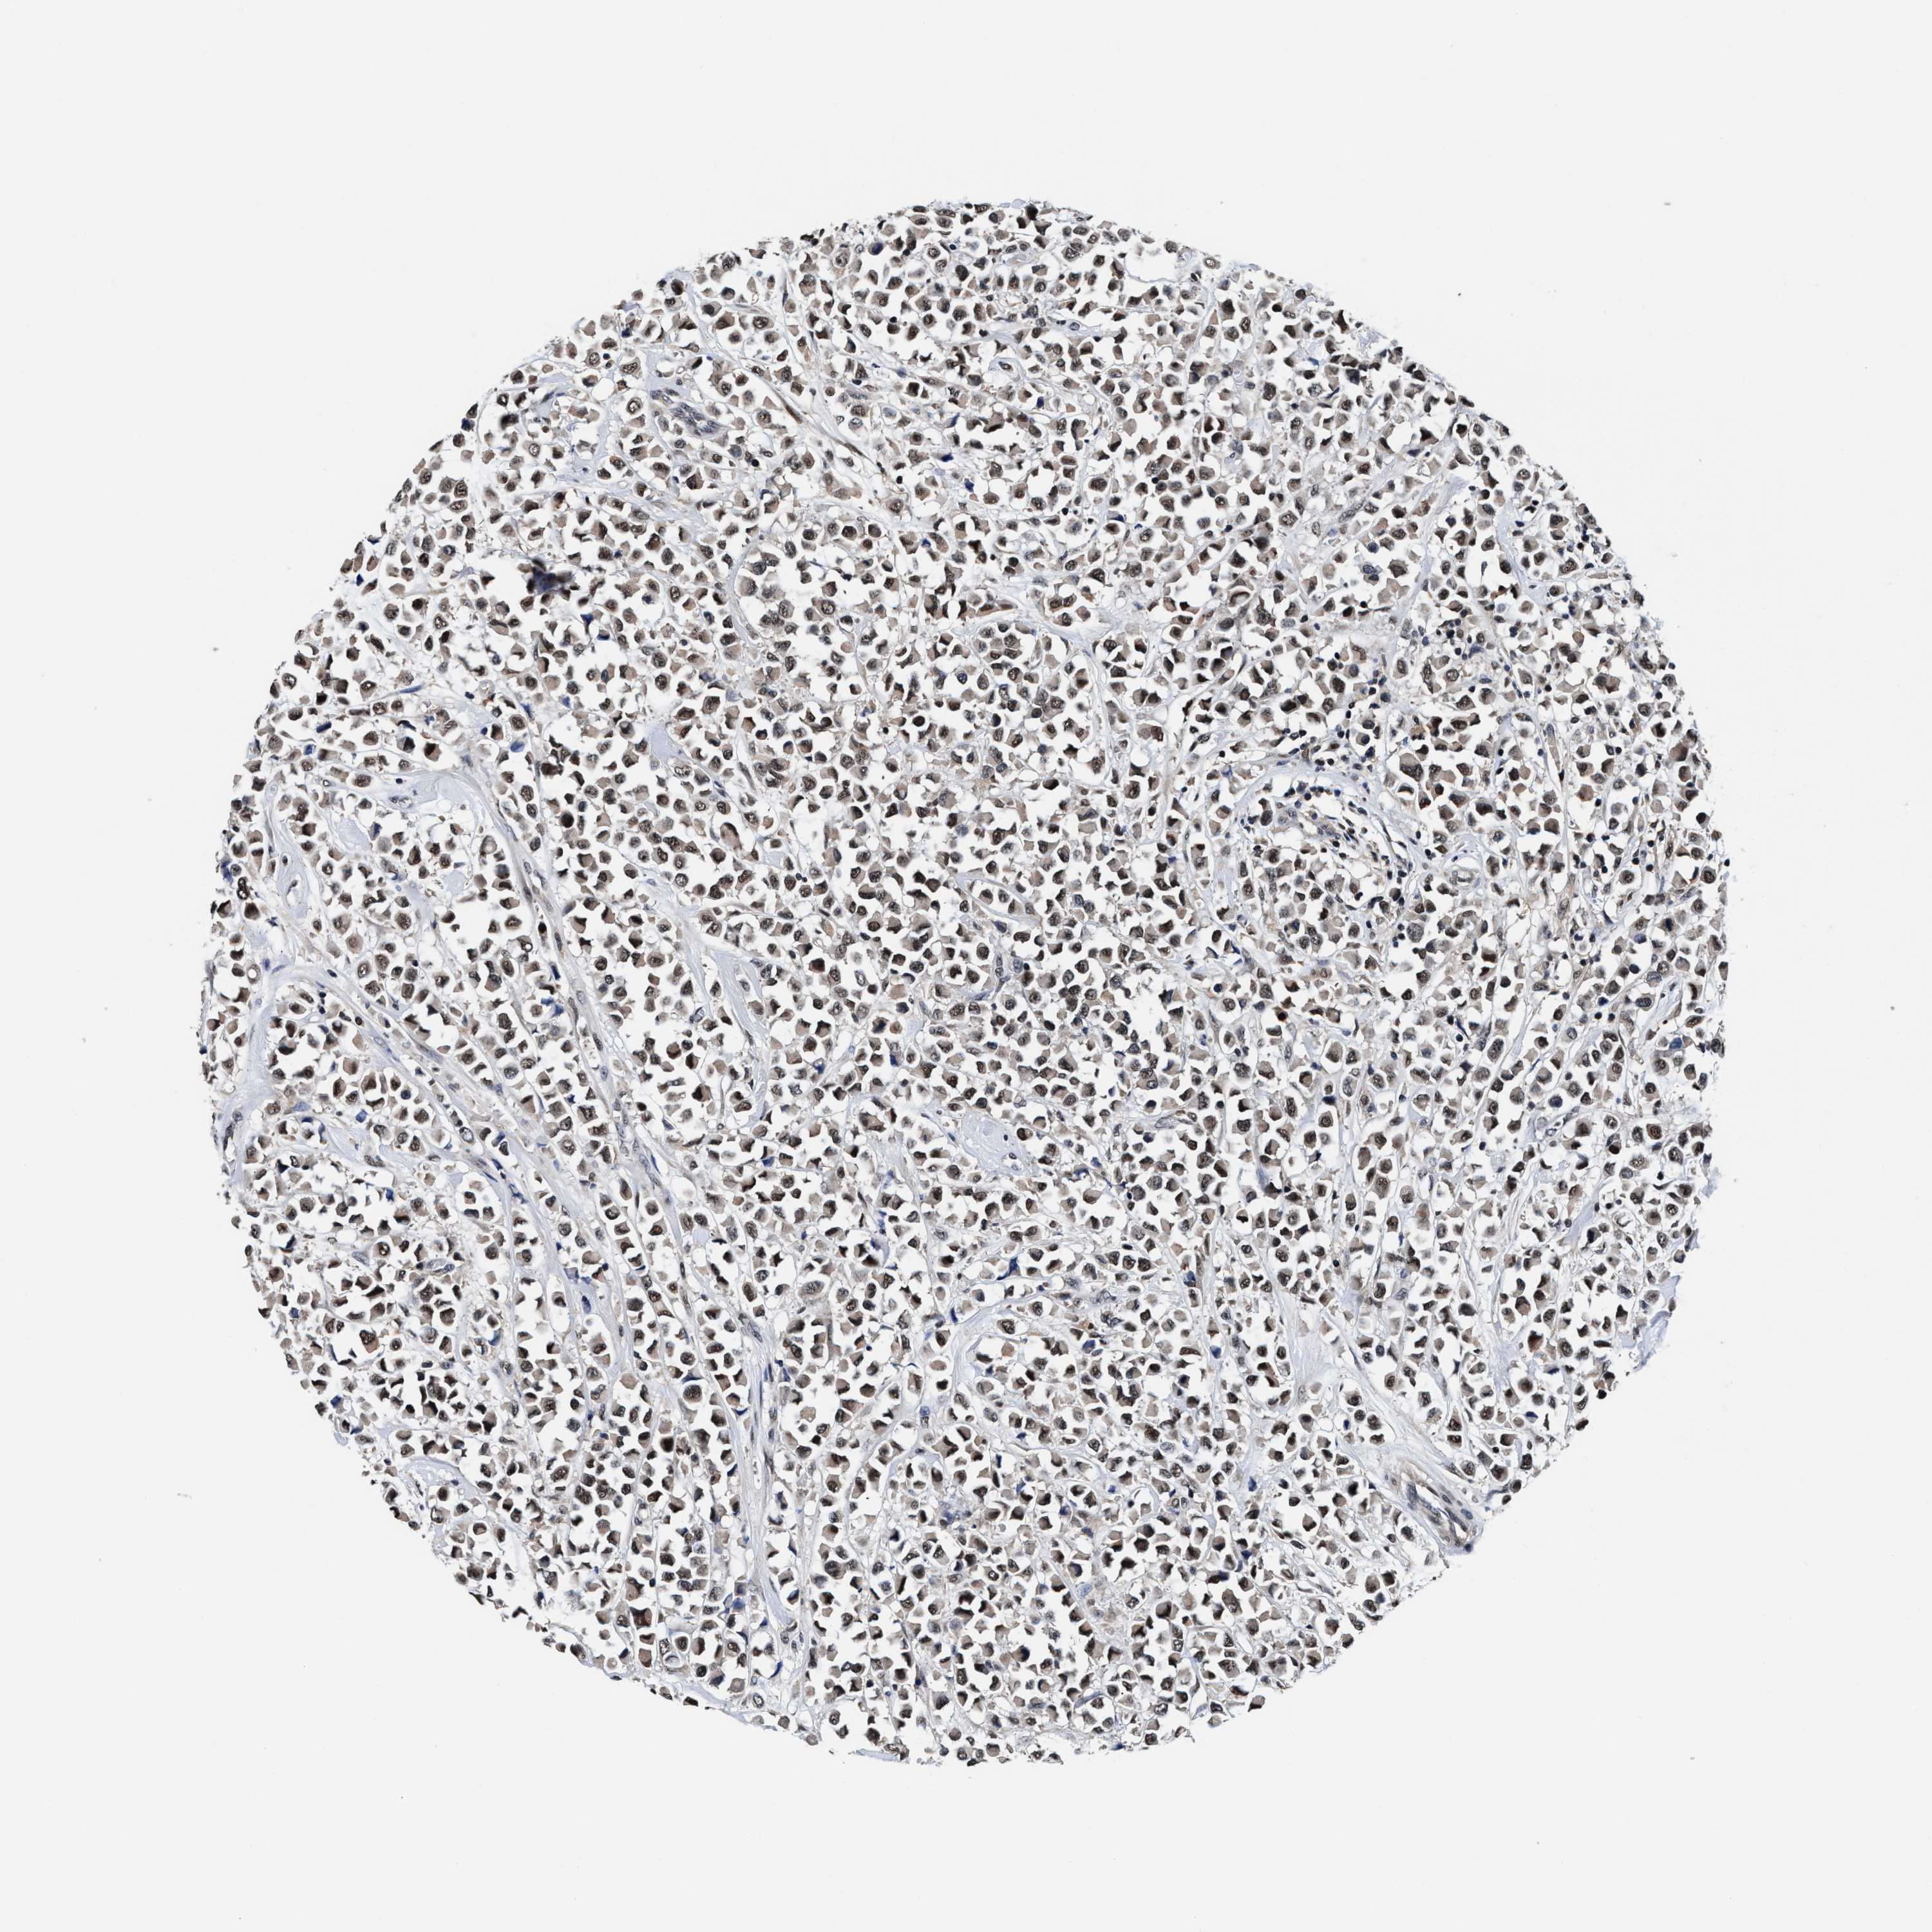

CANCER BREAST CANCER Show tissue menu

BRCA TCGA BRCA VALIDATION PROTEIN EXPRESSION

Breast cancer

Human cancer

USP16 is not prognostic in Breast Invasive Carcinoma (TCGA)